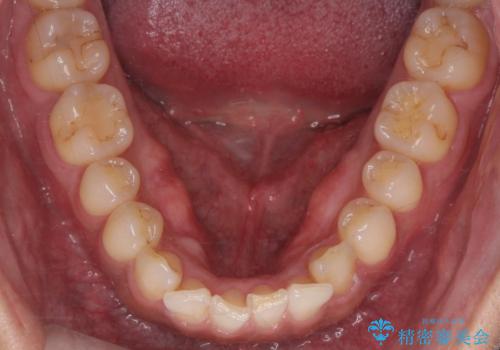

Dr. 岡田康成の症例写真

担当医 岡田康成<2025年10月31日更新>